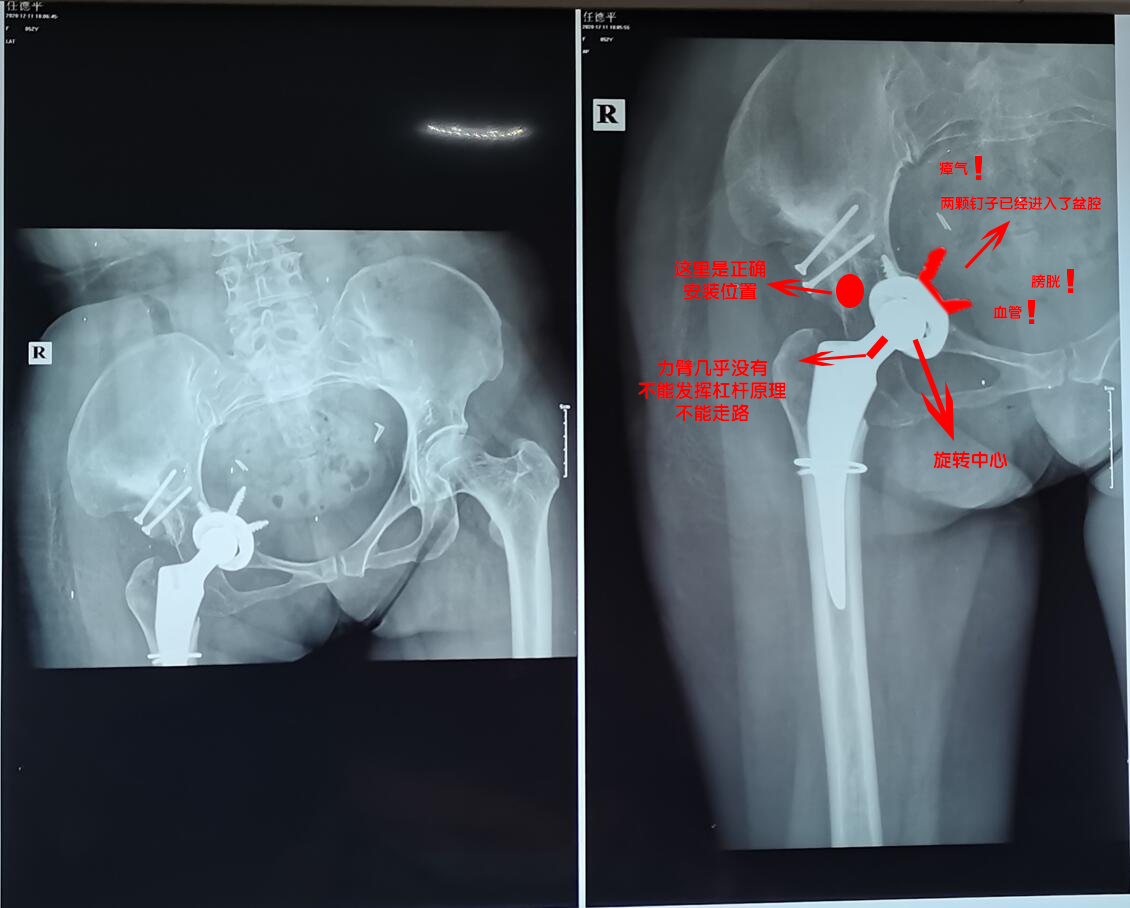

2020年11月25日,该医院对我进行手术治疗,手术名称:右侧人工全髋关节置换手术及造盖成形术、植骨术。结果手术失败了!下面是我手术前后的图片。

如果不是专业人士来发现我的问题,估计我现在都还蒙在鼓里;由于我这个是股骨头坏死,所以需要用假体来替换,但是这家医院技术水平太差,导致这个假体安装位置不正确;从片子中看,假体有部分已经进去了盆腔,甚至在盆腔里还能看见两个耀眼的长钉子,请问这家医院的手术医生究竟要干什么!?盆腔里有大量的脏器、血管、膀胱等等重要的东西,有没有可能这两颗钉子碰到血管和脏器,而且这个地方的骨头还比较薄和脆弱,如果我以后多用力多走路,万一这里破裂了,整个假体进入了盆腔,刺破了血管,我是不是就只能等死了!!出院后,我马上到华西去做检查,专家直接给我说,你这个以后走路的功能是相当差的,知道我和成都中山骨科医院有医疗纠纷,所以说得很委婉,没直接说这个就是一个失败的手术,只是给我分析了他为什么安在这里,安装在这里会对我造成什么影响,缺点在哪里,正确的位置应该安装在哪里!反正是需要进行第二次手术的,不然我以后基本就不要想用这只腿走路了。目前我在成都中山骨科医院花了8万多,然后华西医院喊我准备10万,最佳手术时间为第一次手术后的第6周;华西医院的专家说你这个属于翻修,难度是相当大的!我现在很焦虑啊,睡不着觉!

专家解析这个手术1.jpg 专家解析这个手术2.jpg 专家解析这个手术3.jpg 专家解析这个手术4.jpg 专家解析这个手术5.jpg 专家解析这个手术6.jpg

我手术前右腿比左腿短2厘米,现在右腿做了手术后,发现右腿比左腿长4厘米,相当于差了6厘米,而且右腿的膝盖是向内倾斜的;我的天啊!我现在左脚还要垫一个增高垫,但是还是不行啊,因为差距太大,所以以后走路比以前还要跛。当时进医院的时候,说得好听哦,说尽量给我找平衡点,让我两条腿一样长,现在才发现,他们也只是说说而已。最夸张的是,他们居然手术当中更换材料,术前和我及家属一直沟通的是强生陶对陶材料,我选择也是这个,因为这个材料耐磨、使用寿命长,签字交钱也是交的强生陶对陶材料,没有沟通其它情况,但是他们手术中更换成了聚乙烯材料,这个材料相比陶对陶材料不耐磨、使用寿命短,并且术中没有和家属沟通交流,术后当天也没有任何人对我及家属进行沟通解释,第二天查房的时候才轻描淡写的提了一下;后面医生来解释说由于手术中术中陶对陶材料安装不上,不管怎么说,我认为医院在手术前没有充分做好准备工作,导致陶对陶材料用不上,临时更换的其他的材料。但是你一句安装不上,对我影响得多大,就算你位置安装对了,但是材料用不了多久,意思我过不了几年又要做第二次手术!俗话说:没有金刚钻,别揽瓷器活;我现在真的很后悔去了成都中山骨科医院,因为凭他们目前的实力,做这种手术是有困难的,但是他们还是没有放弃,毕竟做下来8万多,想方设法接下来,不管成不成功,能忽悠一个算一个吧!